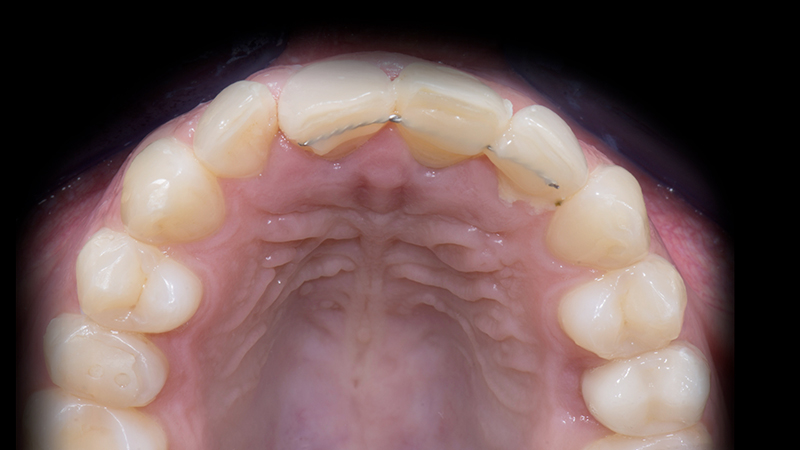

1. Mordenzatura dei denti da 1.3 a 2.3 per fissare il mock-up testato con la tecnica adesiva. Questa decisione mi ha permesso di progettare virtualmente il dente provvisorio 2.1 con una forma cervicale adeguata, copiandola con lo scanner e poi specchiando la nuova morfologia del dente 1.1 con il software di progettazione (Fig. 9d).

2. Rigenerazione ossea dell'alveolo 2.1 con Bio-oss e Muco-graft. In questa fase, il provvisorio fresato è stato cementato ai denti adiacenti con un filo metallico e composito. Dopo 5 mesi, ho ottenut il volume osseo necessario per poter posizionare l'impianto (Fig. 10a, Fig. 10b, Fig. 10c).

Progetto digitale del dente 2.1

Fig. 9d - Progetto digitale del dente 2.1.

Risultato estetico del primo step

Fig. 10a - Risultato estetico del primo step.

Rigenerazione ossea

Fig. 10b - Rigenerazione ossea.

CBCT dopo 5 mesi

Fig. 10c - CBCT dopo 5 mesi.